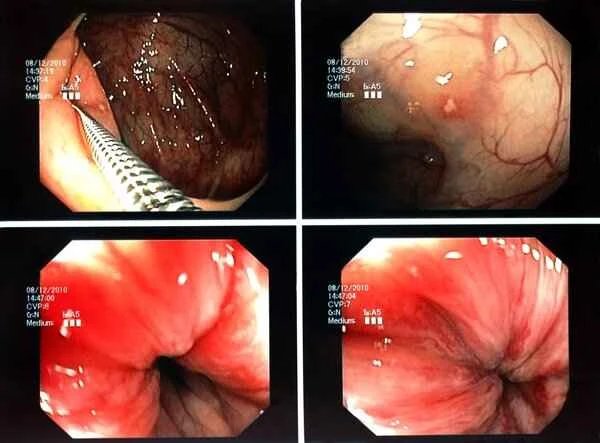

A colonoscopy is a procedure that uses a flexible fiber optic endoscope to examine the inside of the large intestine. During the examination, the doctor can directly observe the intestinal wall through the endoscope and may also perform a biopsy to determine the nature of polyps. While the entire process may be somewhat uncomfortable, it is usually performed with the aid of anesthesia or sedation to ensure patient comfort.

Examination results typically present information such as the size, number, and shape of the polyps. Doctors use this information to determine the nature of the polyps, such as whether they are benign or malignant, and whether further treatment is needed. Understanding the significance of these results is crucial for subsequent treatment decisions. At the same time, we should recognize that all medical examinations have limitations; therefore, maintaining objectivity and rationality when interpreting examination results is very important.